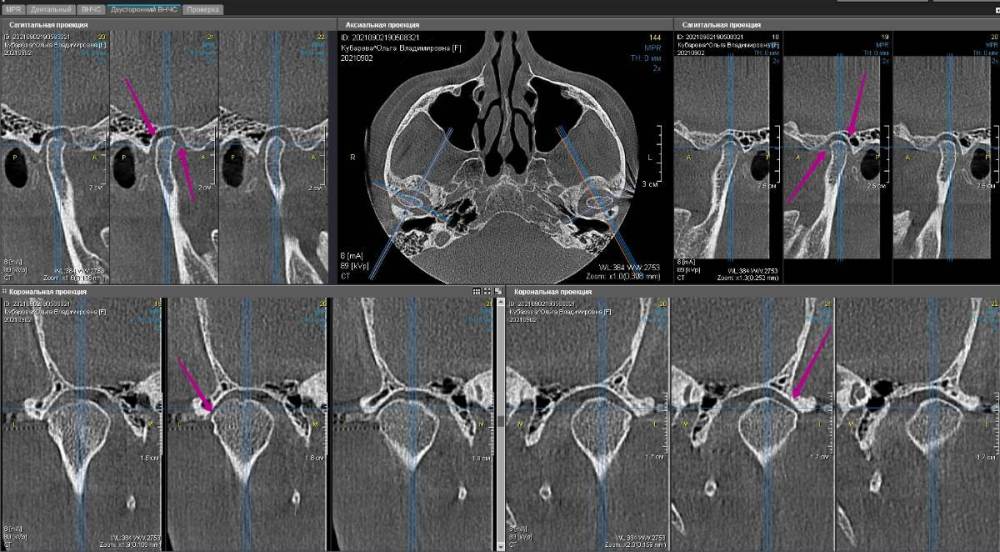

Закончил тотал и решил поделиться. Протезировали с учетом положения ВНЧС в концепции Славичека.  В конце изготовление брукс чекеров для проверки нежелательных контактов во время сна.  Гигиену пытаемся победить...